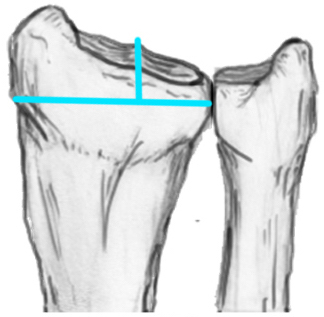

Radial angles

| Volar tilt mean 11° | Radial inclination mean 22° | Radius mean 11 mm longer than ulna |